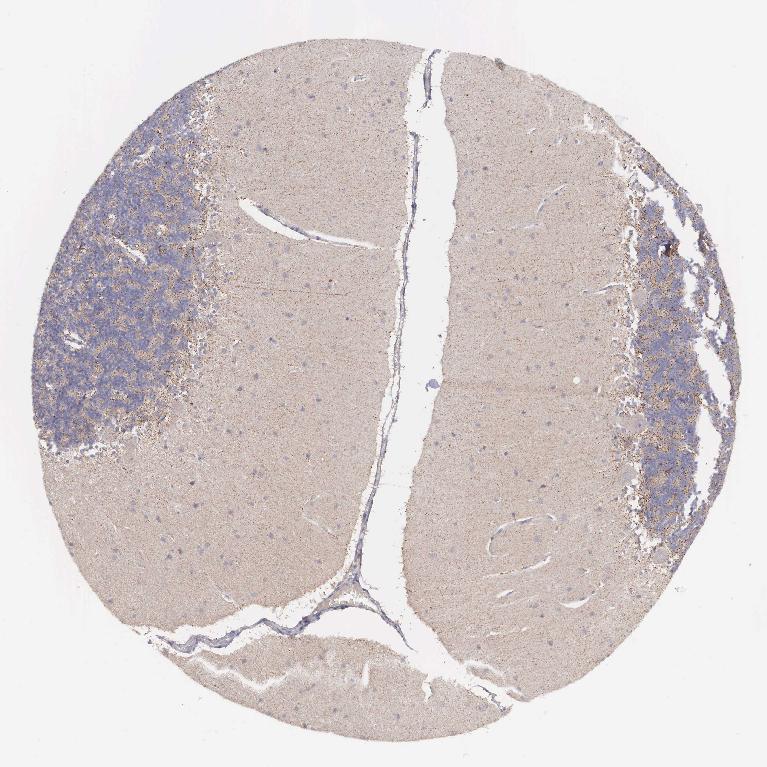

CEREBELLUM - Antibody stainingi

Antibody staining in the annotated cell types in the current human tissue is reported as not detected, low, medium, or high, based on conventional immunohistochemistry profiling in selected tissues. This score is based on the combination of the staining intensity and fraction of stained cells.

Each image is clickable and will lead to virtual microscopy that enables deeper exploration of all samples and also displays staining intensity scores, fraction scores and subcellular localization as well as patient and tissue information for each sample.

Antibody HPA000545

Purkinje cells Not detected

Cells in granular layer High

Cells in molecular layer Low